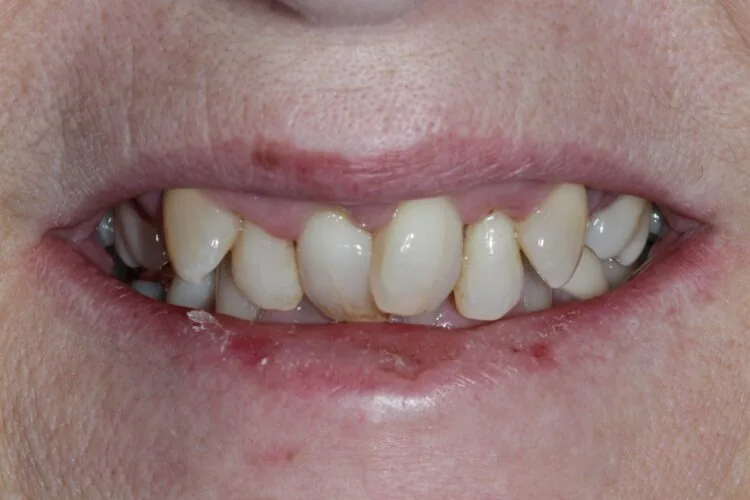

Presenting condition

A comprehensive periodontal examination revealed widespread pocketing and clinical signs of mobility in the anterior region. The upper central and lateral incisors were the most severely affected, and they showed persistent instability despite improvements elsewhere. Generalised recession and attachment loss were confirmed, with periodontal charting from September 2023 and follow-up data in November 2023 demonstrating the extent of disease and its subsequent management.

Pre-treatment images